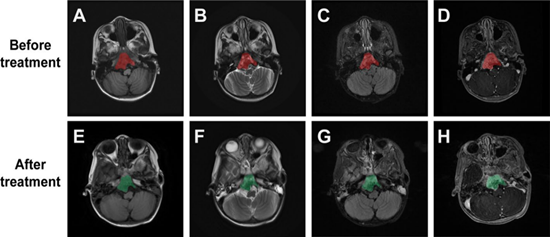

河北一洲肿瘤医院肿瘤内科主任高建芝带领团队在 Discover Oncology 发表的最新研究《19例分化差脊索瘤不同治疗模式临床病例分析》表明:在19例确诊患者中,采用“手术+质子放疗+化疗/靶向/免疫”联合方案后,疼痛、视觉障碍、呼吸道梗阻等主要症状明显改善,病灶体积缩小,局部控制率提高,总生存期与无进展生存期较以往单一治疗模式显著延长。

这一结果验证了以质子治疗为核心的多模式综合治疗在提高治疗安全性和长期预后方面的临床价值,也为今后类似高难度肿瘤的治疗提供了可复制的临床路径。